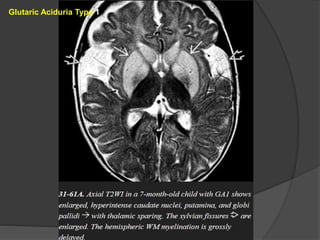

Glutaric Aciduria Type1 Imaging The three "signature" imaging findings of classic GA1 are (1)macrocrania, (2) bilateral widened ("open") sylvian fissures, and (3) bilaterally symmetric basal ganglia lesions. Severe GA1 may also cause diffuse hemispheric WM abnormalities. GA1 infants in metabolic crisis often present with acute striatal necrosis. Bilateral diffusely swollen basal ganglia that are T2/FLAIR hyperintense and that restrict on DWI are typical.

• 86.

Chronic GA1 causesenlarged CSF spaces and atrophy. The volume loss may tear bridging veins that cross from the brain surface to the dura, resulting in recurrent subdural hematomas. GA1 does not enhance on T1 C+ scans. MRS is nonspecific with decreased NAA, increased Cho:Cr ratio, and (during crisis) elevated lactate level. Glutaric aciduria type 2 (GA2) Imaging studies show symmetric T2/FLAIR hyperintensity in the basal ganglia and hemispheric WM, but the "open" sylvian fissures characteristic of GA1 are absent.